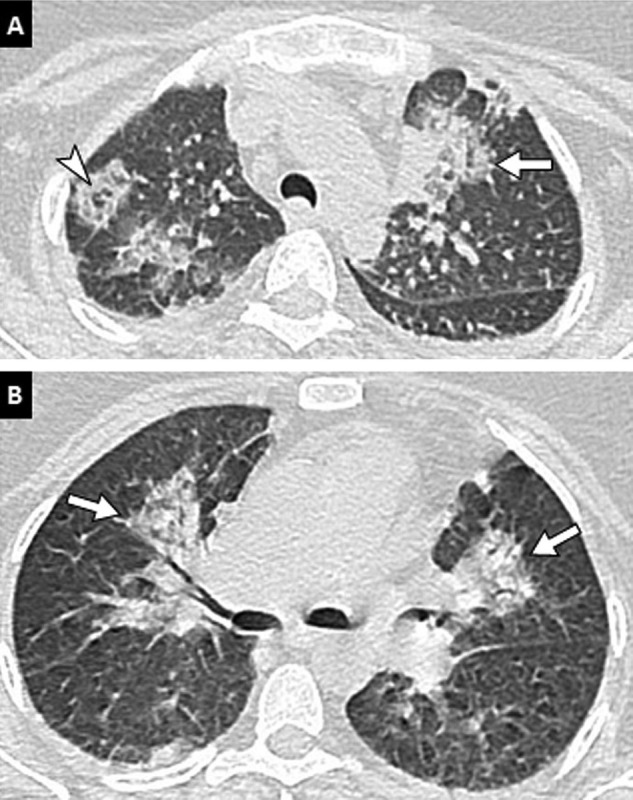

Fig. 2.

Unenhanced CT examination in a 26-year-old woman with COVID-19 pneumonia. Unenhanced CT image of the chest (lung window: W1600/L-500 HU) in the axial plane reveals apical and perihilar predominant pulmonary lesions (arrows) with a “reverse halo sign” (arrowhead).

Fig. 3.

75-year-old man with history of chronic bronchiolitis recently diagnosed with COVID-19 pneumonia. (A, B, C) Chest CT images in the axial plane show multifocal, patchy, ground-glass opacities (arrows) as well as diffuse thickening of bronchial walls (arrowheads). (D, E, F) The diagnosis of COVID-19 pneumonia was facilitated by the comparison with chest CT images obtained 2 months earlier that already showed bronchitis and bronchiolitis (arrowheads) but no lung opacities.